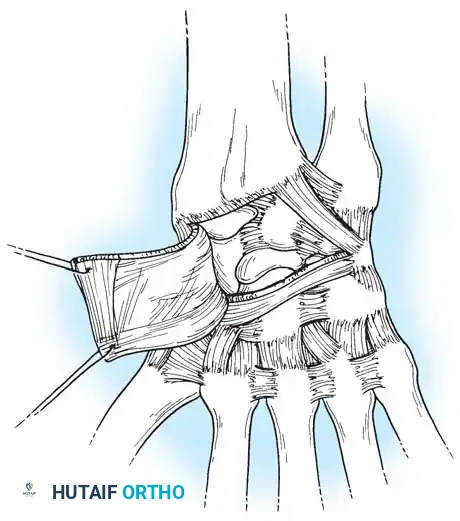

- Positioning and Incision: The patient is positioned supine with the arm on a hand table. A longitudinal dorsal incision is made centered over Lister’s tubercle, extending distally to the base of the third metacarpal.

- Exposure: The extensor retinaculum is elevated, and the extensor pollicis longus (EPL) is transposed radially. The dorsal capsule is excised to expose the radiocarpal and midcarpal joints.

- Joint Preparation: The dorsal cartilage of the radiocarpal, intercarpal, and third carpometacarpal joints is meticulously denuded down to bleeding subchondral bone.

- Bone Grafting: A local distal radial bone graft portal is utilized. Cancellous bone is harvested from the distal radius metaphysis to augment the fusion sites.

- Plate Application: A 3.5-mm dynamic compression plate (DCP) is applied from distal to proximal. The plate is specifically contoured to provide 10 to 15 degrees of wrist extension. The plate spans the local radial bone graft augmentation, ensuring rigid compression across the fusion mass.